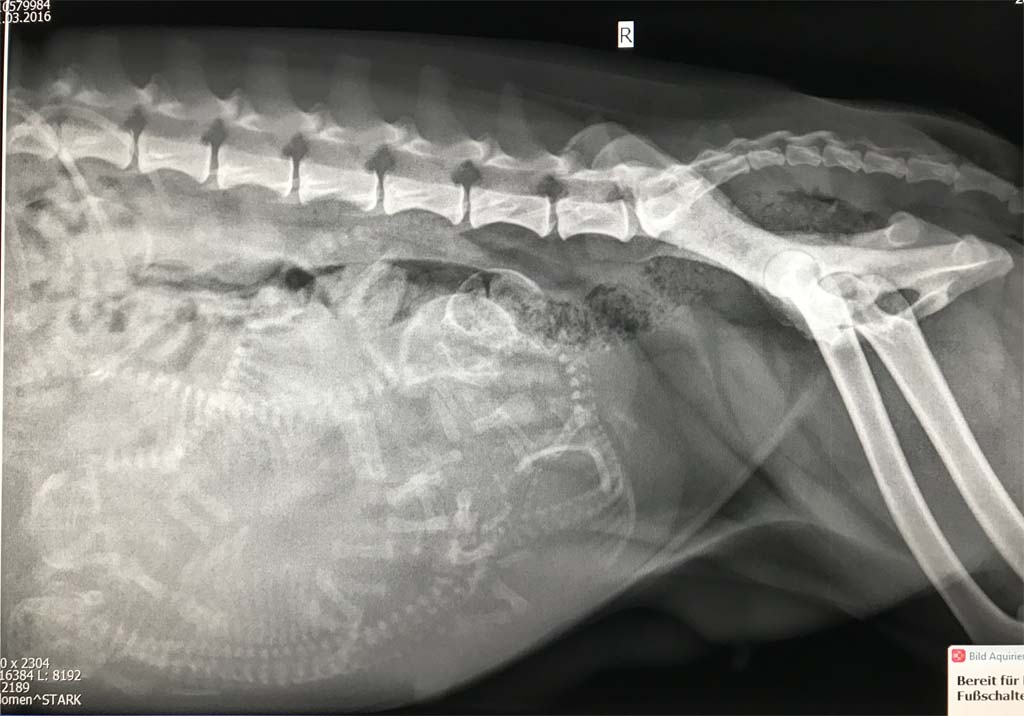

Die kommenden Tage werden wir Seven nun engmaschig überwachen und nicht nur Gewicht, sondern insbesondere ihre Temperatur. Wir hoffen natürlich auf eine reibungslose Geburt von den Zwergen. Wieviele es sind? Anbei die Aufnahmen von heute .... so kann jeder mal versuchen zu zählen ;-).

Seven am Tag 57 ihrer Trächtigkeit